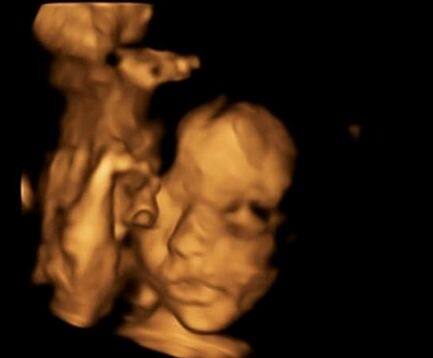

OMG! भ्रूण को थी ये गंभीर बीमारी, डॉक्टर्स ने गर्भ से निकाल कर ठीक कर दी और फिर वापिस गर्भ में डाल दिया

सिम्पसन का कहना है कि उसकी इस सर्जरी के दौरान आसपास दुनिया के सर्वश्रेष्ठ डॉक्टर्स थे जिन्होंने इस सर्जरी को अंजाम दिया. यूके की ये ऐसी पहली सर्जरी है जिसे सफलतापूर्वक ऑपरेट किया गया है.

डॉक्टर्स ने शुरूआत में सिम्पसन को एबॉर्शन करवाने की सलाह दी लेकिन सिम्पसन ने इसके लिए मना कर दिया. फिर डॉक्टर्स ने फेटल सर्जरी का विकल्प दिया जिसे सिम्पसन और उनके पति मान गए.